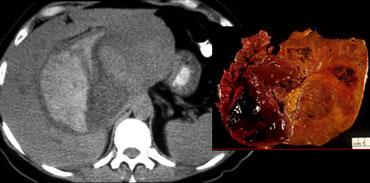

Bên trái là một bệnh nhân khác với HCC.

Chỉ trong thì cân bằng mới thấy bao xơ tương đối tăng tỷ trọng.

Hình ảnh bên trái được chụp 8 phút sau khi tiêm thuốc cản quang.

Lưu ý rằng bản thân khối u tương đối giảm tỷ trọng trong thì cân bằng.

Như vậy, khối u có hiện tượng thải thuốc nhanh (washout).